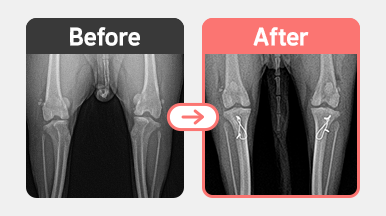

[요골 골절 수술] 푸들 / 4살 / 좌측 radius 골절

2025-11-21